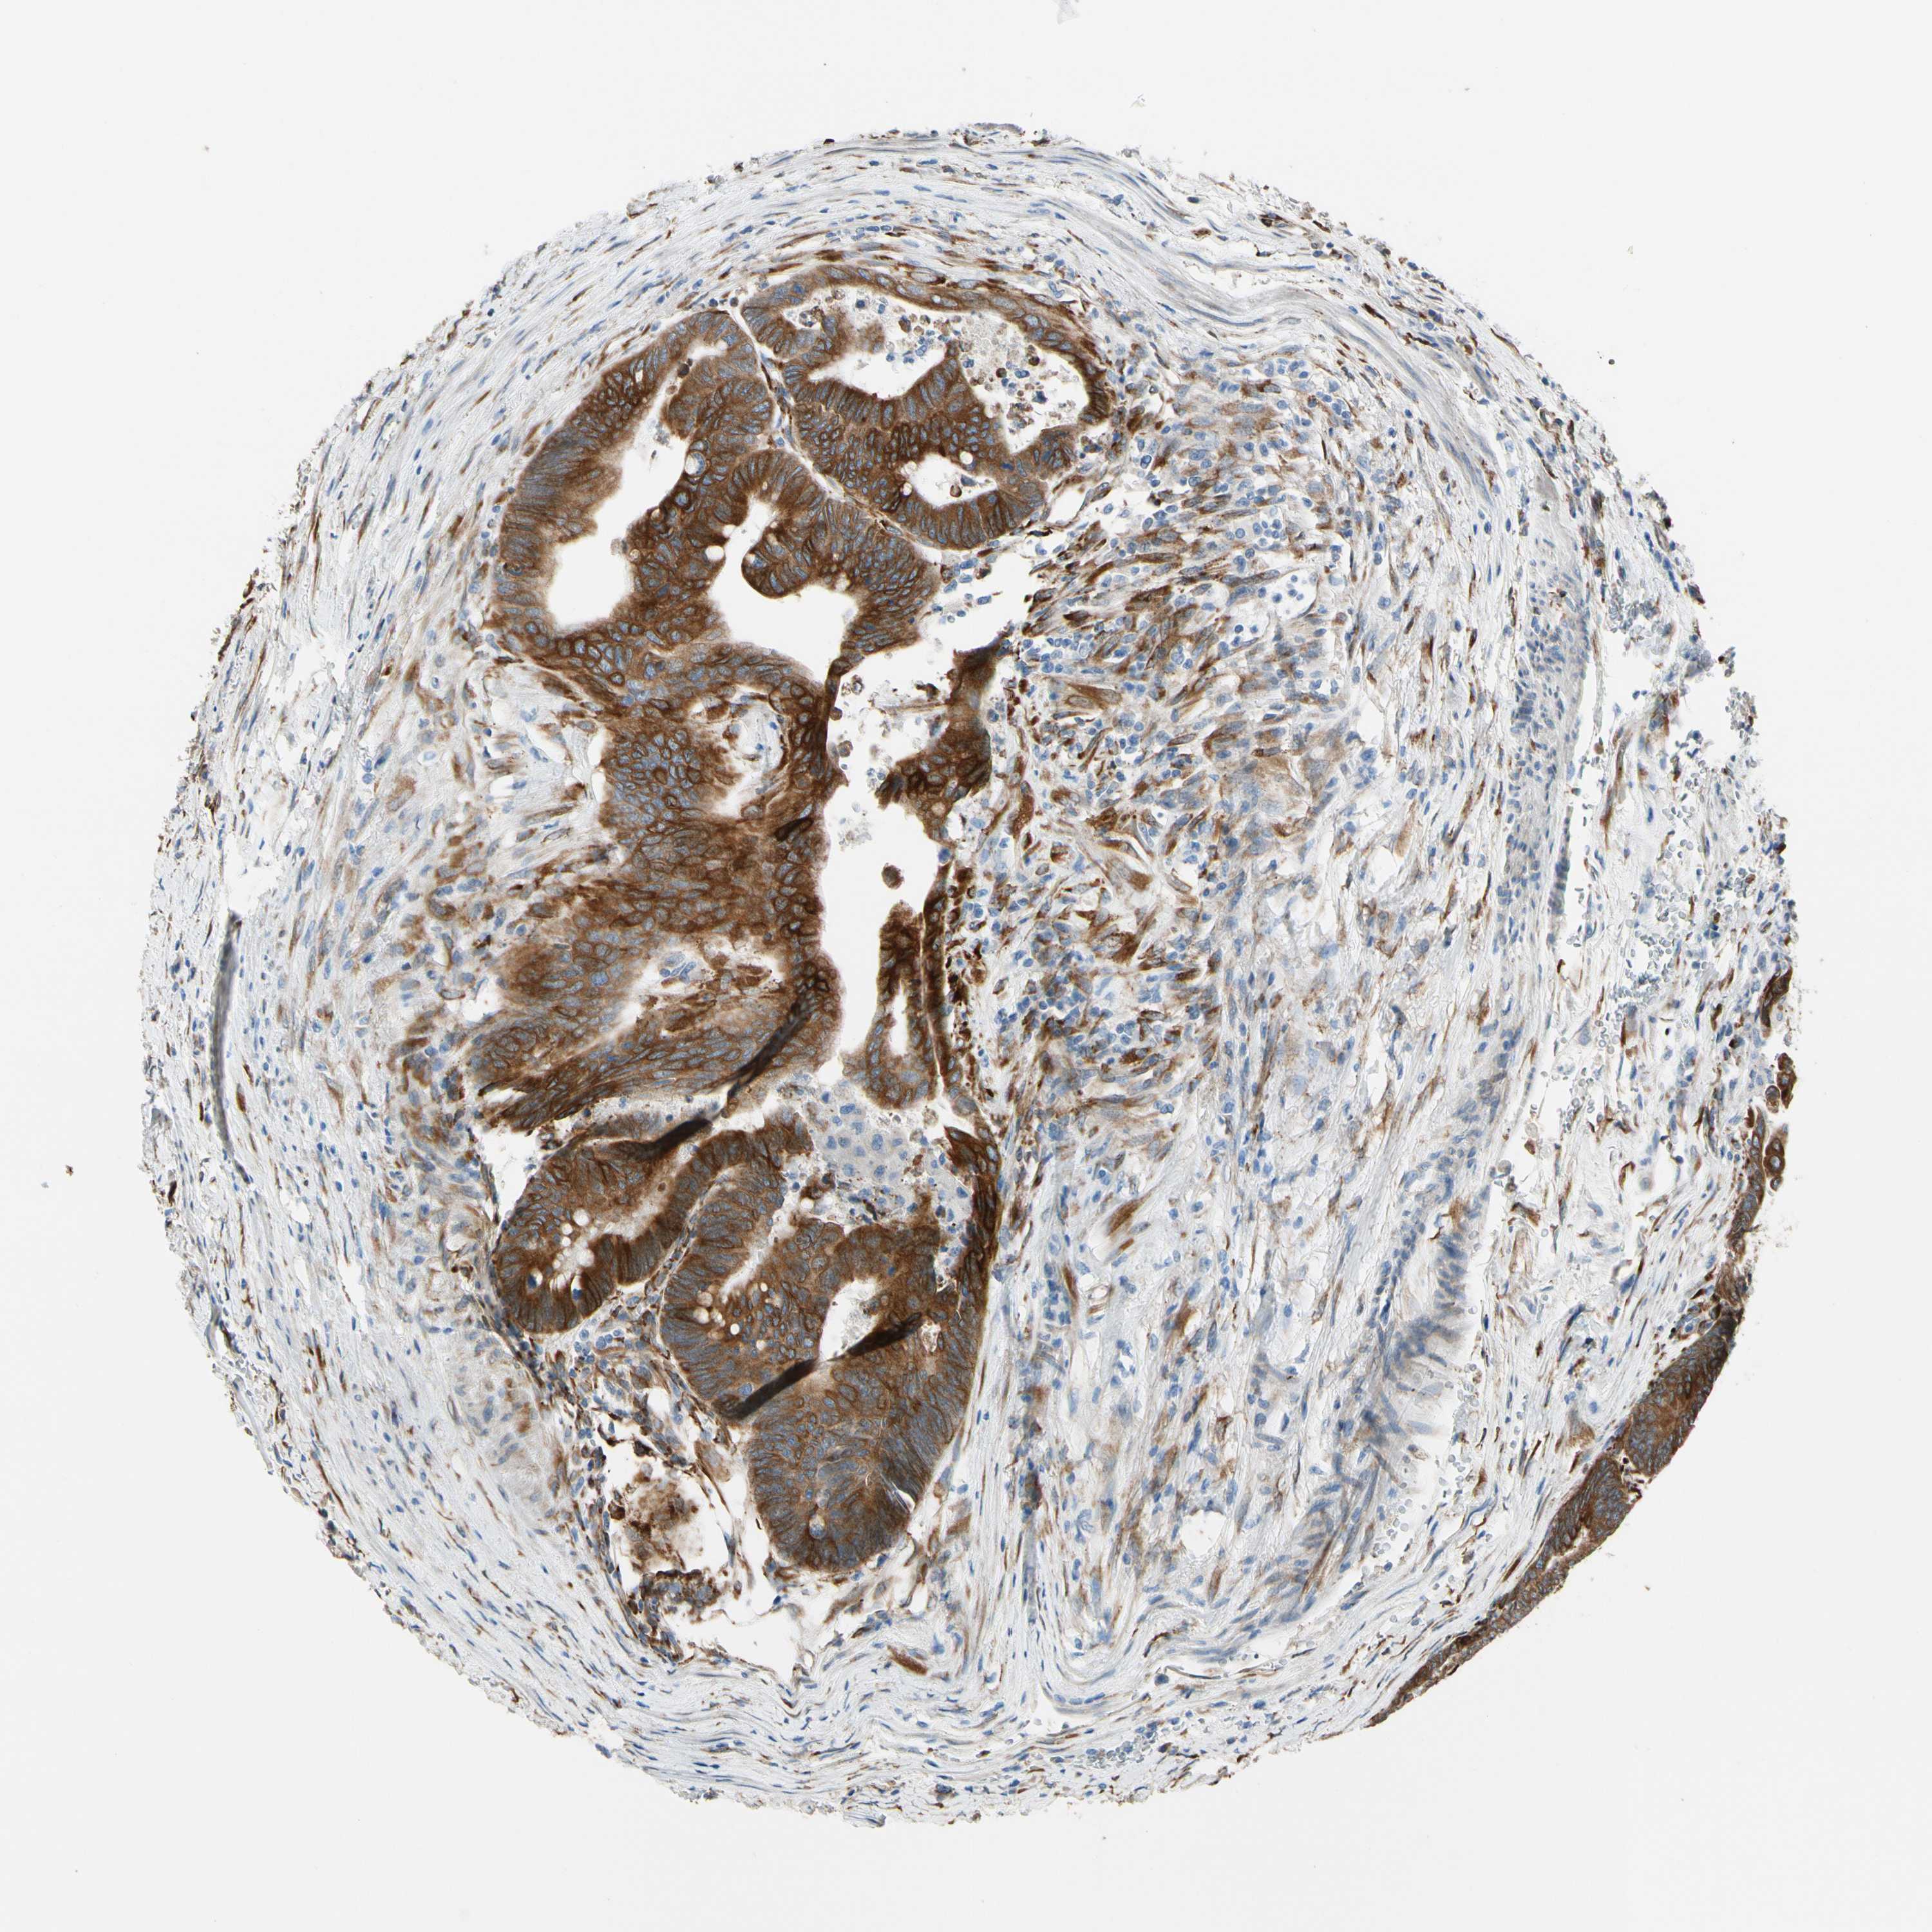

CANCER COLORECTAL CANCER Show tissue menu

Colorectal cancer

Human cancer

Colon adenocarcinoma